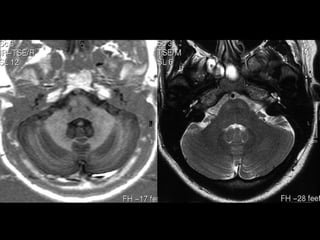

• PONTE - COLÍCULOS FACIAIS

• PEDÚNCULOS CEREBELARES MÉDIOS / CORPOS MEDULARES

• CEREBELO

VÉRMIS - NÓDULO, ÚVULA, PIRÂMIDE

• CISTERNA      HEMISFÉRIOS

PRÉ-PONTINA

• C.A.I.       CEREBELO-PONTINA